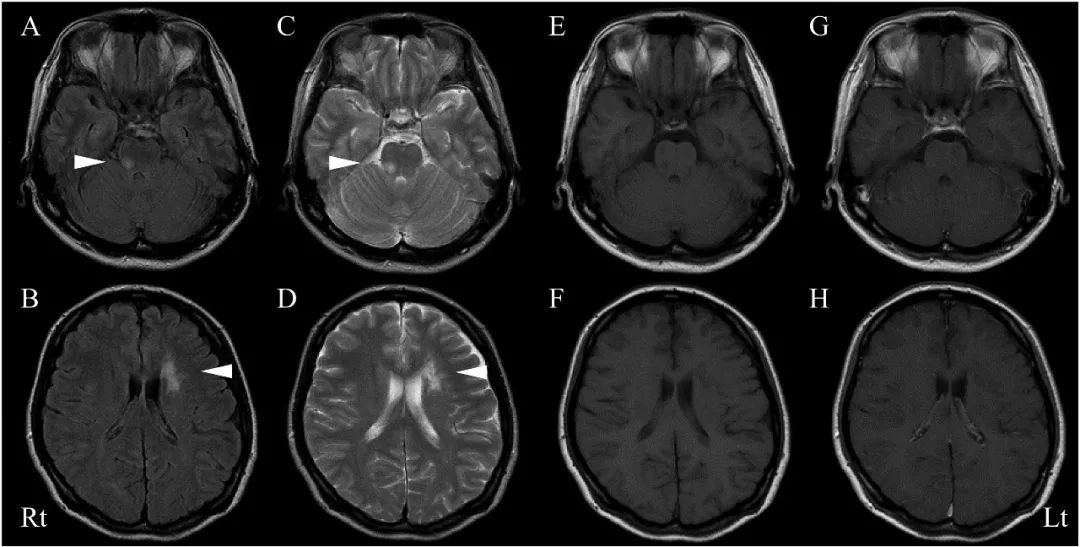

2009年11月,患者左手感觉迟钝、左臂和腿部出现沉重感,于12月再次入院。入院时查体显示血压为123 /77mmHg,脉搏为73bpm,体温为36.7°C;神经系统检查显示眼球跳动,左侧痉挛性偏瘫,左侧感觉障碍。眼科检查显示视力正常,未观察到葡萄膜炎。头颅MRI T2WI和FLAIR图像显示脑桥右上侧高信号病灶(图2)。

图2

头颅MRI FLAIR(A)和T2WI(C)显示脑桥右上方高信号病灶。T1WI增强(G)显示部分增强。FLAIR(B)和T2WI(D)也显示侧脑室左前角、左侧丘脑和壳核存在高信号改变,考虑为陈旧病灶。